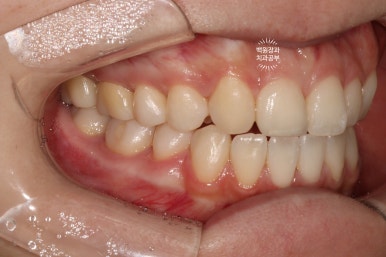

왼쪽: 우측 측면사진, 오른쪽: 좌측 측면사진

고개를 돌려 촬영한 사진을 보시면, 더욱 확실히 확인이 가능하실거에요.

우측 측면사진에 앞니가 하나 부족합니다. 정확히 얘기하면 대문니 - 중절치가 없죠.